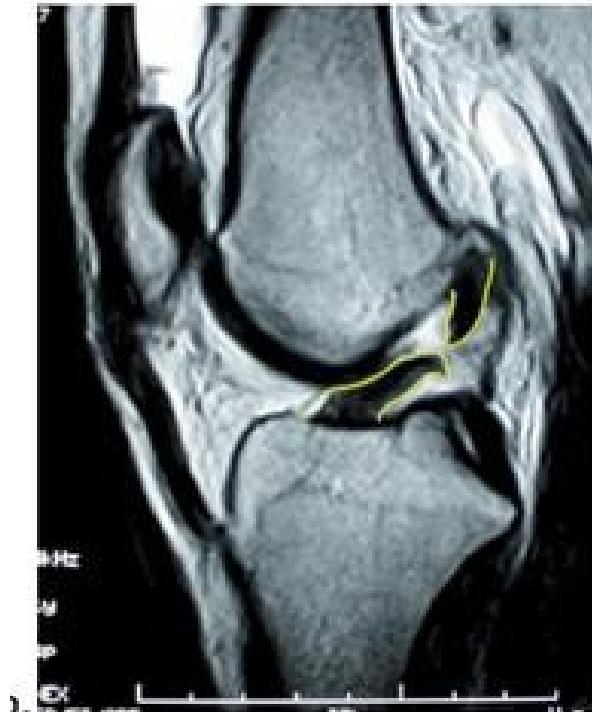

| ACL & PCL: Anterior/Posterior Drawer Test OR Lachman’s test OR Pivot Shift test | Assess integrity of Anterior and Posterior Cruciate Ligaments specifically | Anterior/Posterior Drawer Test: Lachman’s test: ![]() | Excessive anterior or posterior translation of the tibia, indicating ACL or PCL injury | |

| Meniscus: McMurry’s test OR Medial & Lateral joint tenderness Apley grinding test | Assess for meniscal tears | McMurry’s test: Apley grinding test: ![]() | Click, thud, or pain during knee flexion, extension, and rotation during McMurray’s; pain during compression and rotation during Apley’s. | |